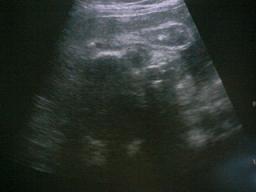

2007年6月27日撮影。

32w2d

FL(大腿骨長)=5.59センチ

推定体重=1825グラム

またA左の写真はわかりにくいので右の写真で図解!

今回の検診でも逆子ちゃんだったうちのかわいいベビちゃん。

モニターで見るとまるでムンクの叫びのような格好をしてました^^;

とりあえず次回の検診で逆子ちゃんが直っていなかったら帝王切開の予定でレントゲンなど、いろいろ検査をするみたいです><